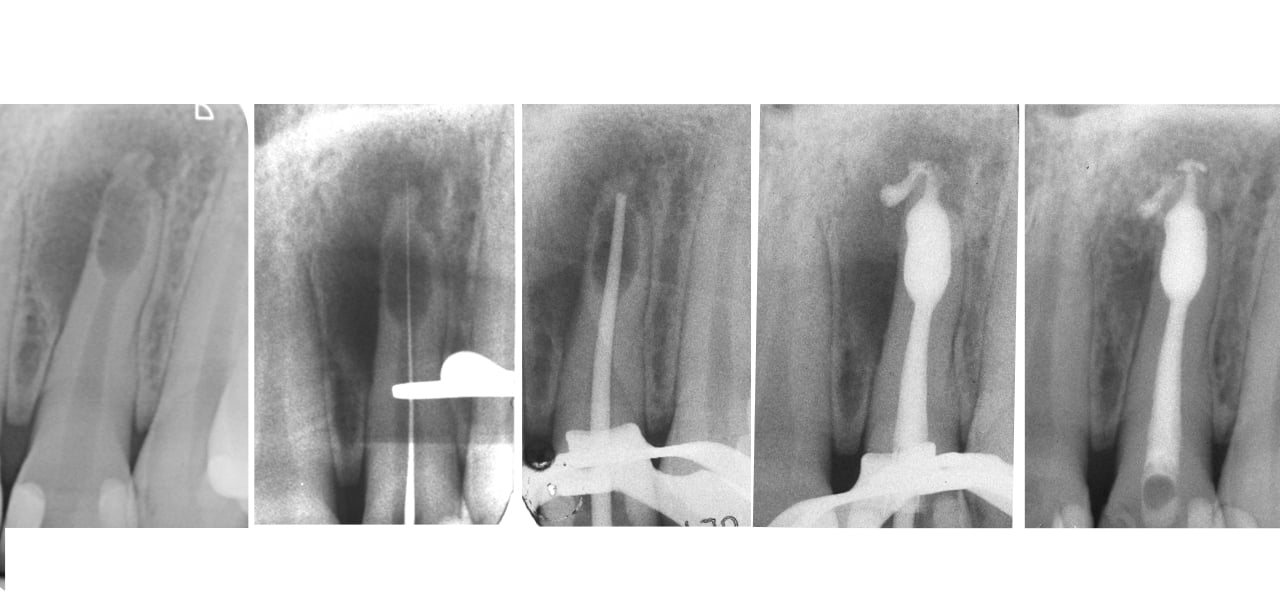

Caso clinico 1. Incisivo laterale con lesione periapicale e ampio riassorbimento interno del terzo apicale. Dopo il trattamento endodontico, l’otturazione canalare ha consentito un completo riempimento dello spazio patologico e del sistema canalare. La radiografia di controllo a 3 anni evidenzia la completa risoluzione della patologia periapicale (Chiara Pirani).